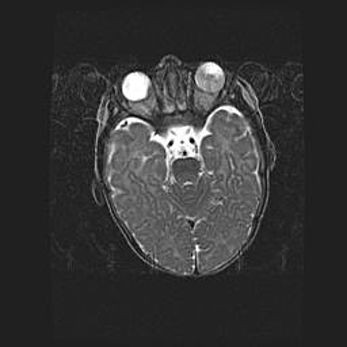

Подострая гематома правой гемисферы мозжечка.

Наружная гидроцефалия.

Возраст: 15 дней

Вес: 3100 г

Пол: женский

Окружность головы: 37 см

Срок гестации: 35-36 недель

При открытой наружной форме гидроцефалии у новорожденных расширяются и переполняются субарахноидные пространства.

Кровоизлияния в мозжечок имеют две клинико-анатомические формы: полушарные гематомы и кровоизлияния в червь.

К появлению этой патологии может привести: повреждения головного мозга, возникающие в результате асфиксии и гипоксии плода при беременности, или травмы во время родов. Редко гематома мозжечка может быть результатом первичной коагулопатии и сосудистой мальформации, диссеминированном внутрисосудистом свертывании, изоиммунной тромбоцитопении.